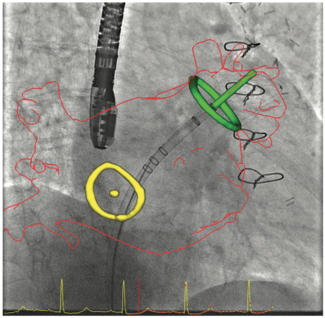

This case illustrates how robotic-assisted percutaneous coronary intervention (PCI) can be leveraged in a complex case involving multilevel arterial occlusive disease.